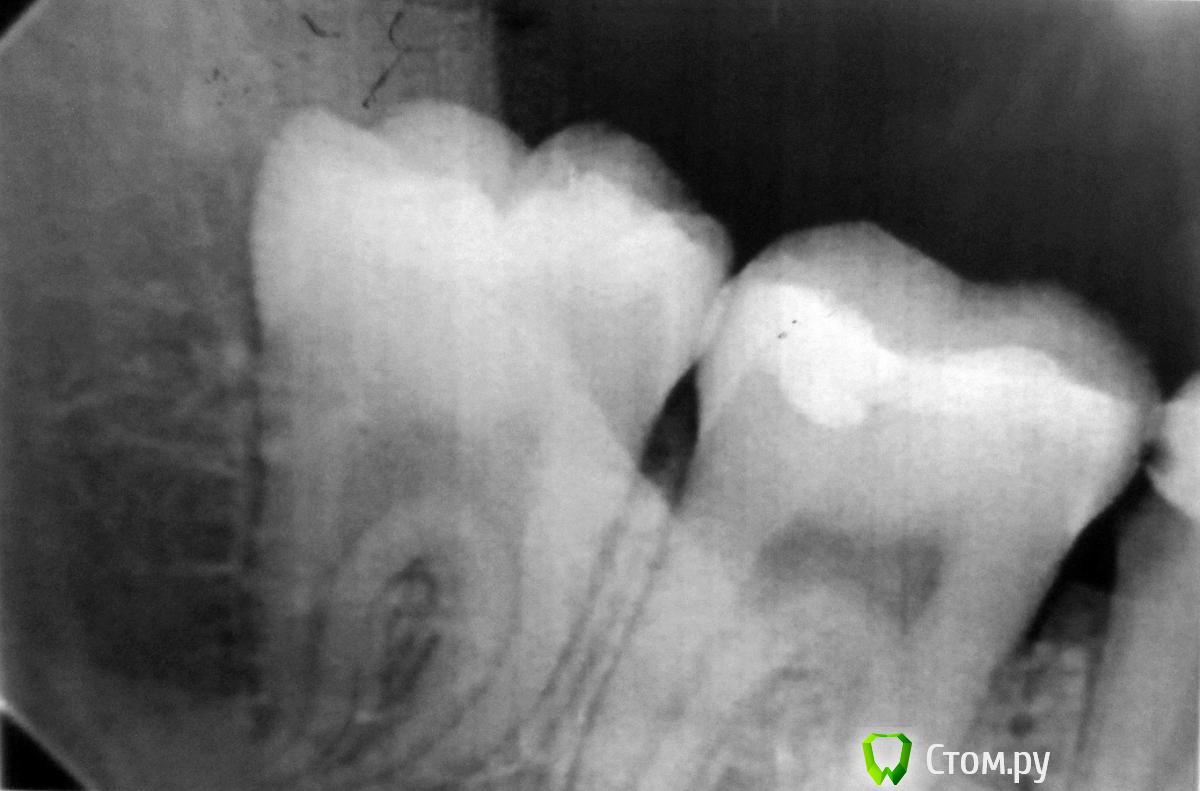

Kukucapol Опубликовано 13 октября, 2014 Поделиться Опубликовано 13 октября, 2014 Здравствуйте.Помогите советом, нахожусь сейчас вне дома, начала расти восьмерка. Отекла десна, припухла щека, частично боль отдает в горло. Больно открывать рот, жевать. Обезболивающие помогают слабо. Сегодня была у стоматолога, сделала рентген (прикрепляю к посту, качество не очень ввиду того, что не взяла его в цифровом виде). Врач прописал антибиотики и сказал, что зуб нужно удалить. А я переживаю, может быть можно обойтись иссечением десны? Толково побеседовать со стоматологом не вышло ввиду отсутствия в моем лексиконе необходимых фраз для описания своего состояния врачу на его языке. Так ли необходимо удалять этот зуб? Буду благодарна за совет. Заранее спасибо. Ссылка на комментарий